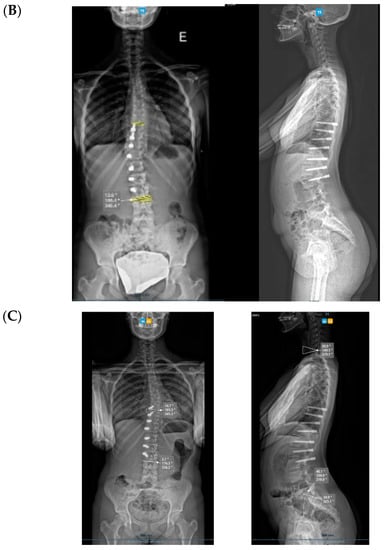

Spinal growth is difficult to assess accurately in a coronal deformity that is gradually improving by the surgical procedure in a spine that is still growing, as the two chosen spots will gradually distance away from each other through these two mechanisms. We have taken the same midpoint in the distal endplate of the instrumented vertebra or on the proximal endplate, which is always on the same proximal junctional vertebra (Figure 8). Over this period of 6 months, the referred distance has increased by a mean of 7 mm (min. 3–max. 16 mm) in the three cases, and the oldest girl (56.7° Cobb angle pre-op) saw the greatest increase. In the case of such flexible scoliosis with a more severe Cobb angle that corrected significantly with this technique (Figure 8 and Figure 9), it is obvious that the two chosen spots will distance more from each other than in scoliosis with a smaller Cobb angle. This increase in spinal length between the two endplate spots is not spinal growth per se, but differentiating these two mechanisms is difficult.

Figure 8.

Measuring “spinal length” between two spots in two different spines shows the difficulty in interpretation.

Figure 9.

Over-correction. (A) Pre-op (left) + 18-month FU (curvature apex corrects to the opposite side) (right). (B) Post tether release. (C) Immediate post-op erect radiograph.

3.1. Complications

The only case with a 15-month follow up progressed to coronal over-correction and had to be revised (under local anaesthetic) for tether release at four levels (Figure 9A,B). Since then, she has been doing well clinically and radiologically. This complication may have happened because correction obtained at the index procedure was too much, with a Cobb angle of 13.6° in the immediate post-operative erect radiograph (pre-op Cobb angle 56.7°) in a girl rated Sanders 3 (Figure 9C).